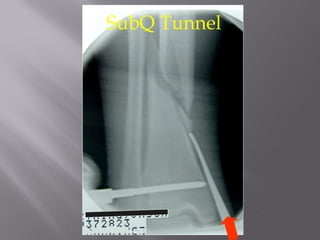

SubQ Tunnel

Insert plate